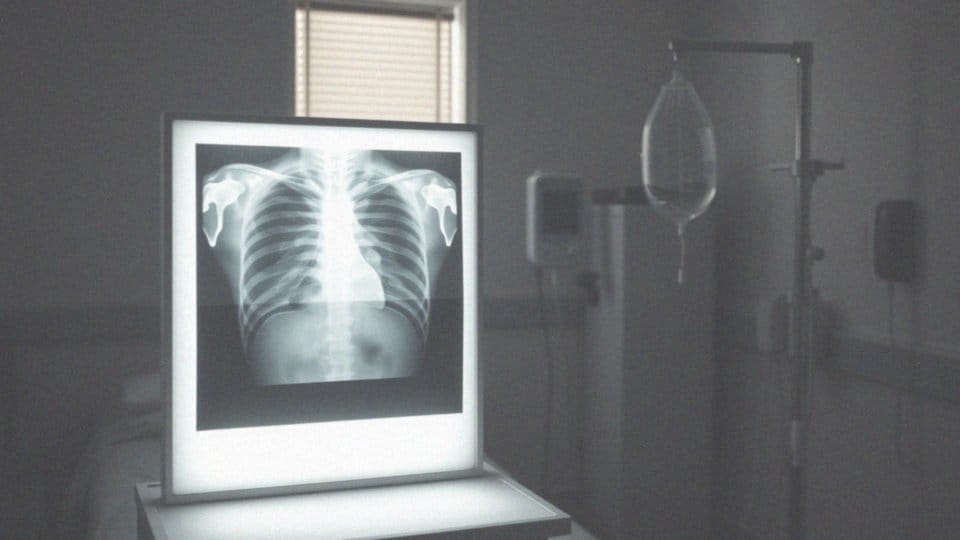

Kiedy pojawiają się objawy, takie jak trudności w oddychaniu, nie należy zwlekać — warto jak najszybciej zasięgnąć porady lekarza. W procesie diagnozy wykorzystuje się zdjęcia rentgenowskie klatki piersiowej oraz ultrasonografię, które pomagają określić ilość nagromadzonego płynu i dokładne miejsce jego występowania.

Kolejnym krokiem jest badanie fizykalne, podczas którego lekarz sprawdza wydolność oddechową pacjenta. W diagnostyce istotne są także badania obrazowe. RTG klatki piersiowej oraz ultrasonografia (USG) odgrywają kluczową rolę w identyfikowaniu obecności płynu w jamie opłucnej oraz w ocenie jego objętości i umiejscowienia. W bardziej złożonych przypadkach lekarz może zlecić tomografię komputerową (TK), aby uzyskać bardziej szczegółowe obrazy.

W diagnostyce problemów z płucami przeprowadza się różne badania, które pomagają wyjaśnić przyczyny gromadzenia się płynu. Do najważniejszych metod diagnostycznych należą:

- RTG klatki piersiowej, które skutecznie wykrywa płyn w jamie opłucnej,

- badanie ultrasonograficzne (USG), które dostarcza szczegółowych informacji na temat ilości oraz lokalizacji płynu, a także wspomaga procedury, takie jak torakocenteza,

- tomografia komputerowa (TK) klatki piersiowej, która umożliwia ocenę nie tylko płuc i opłucnej, ale również śródpiersia,